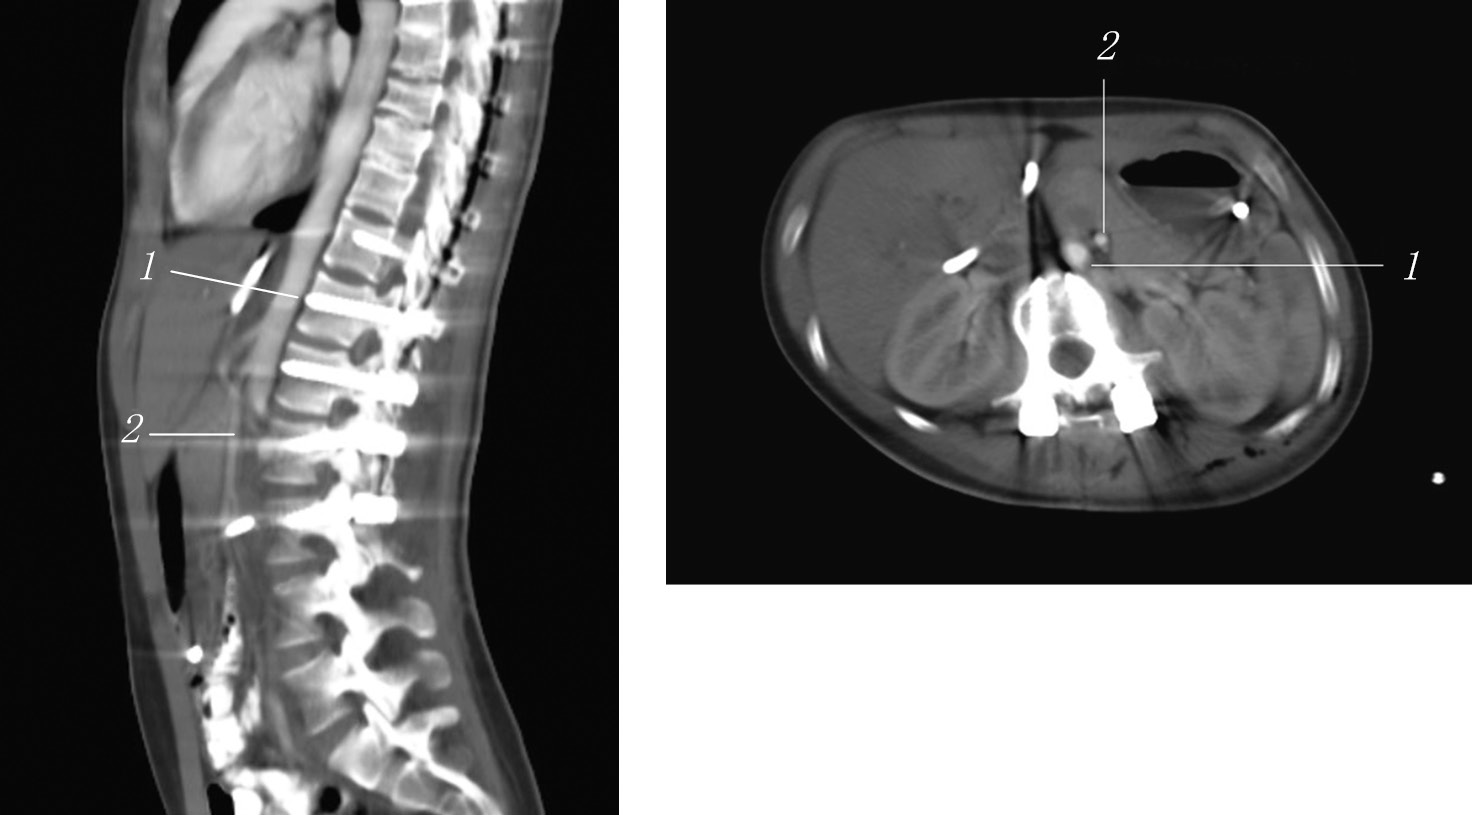

A combined MSCT with contrasting of the gastrointestinal tract and angiography of the abdominal cavity vessels was performed (Fig. 6). In specific, a tube was installed to the level of the duodenum, without distal disturbances in the contrast agent passage. Contrast agent traces in the small and large intestine were found. The stomach was not enlarged, the gas bubble was 110 × 40 mm, and the contents were traces of fluid. When contrasting of the vessels, the aortic–mesenteric angle was 7.7° (normal is 25°–60°), and the aortic–mesenteric distance was 5.1 mm (normal is 10–28 mm), which is a sign of SMA syndrome.

Fig. 6. Combined multispiral computed tomography with contrasting of the gastrointestinal tract and angiography of the vessels of the abdominal cavity: 1 — aorta; 2 — superior mesenteric artery

For 1.5 months, the patient received conservative therapy, during which complete assimilation of food introduced through the mouth and independent emptying of the intestine were achieved. On the control CT angiography, the aortic–mesenteric angle was 17° (norm 25°–60°), and the aortic–mesenteric distance was 13 mm (norm 10–28 mm) (Fig. 7). However, the patient continued to eat in small portions and experienced discomfort and nausea after eating a large amount of food. To select further treatment approach, monitoring by an abdominal surgeon was recommended to the patient.

Fig. 7. Control computed tomography: 1 — aorta; 2 — superior mesenteric artery